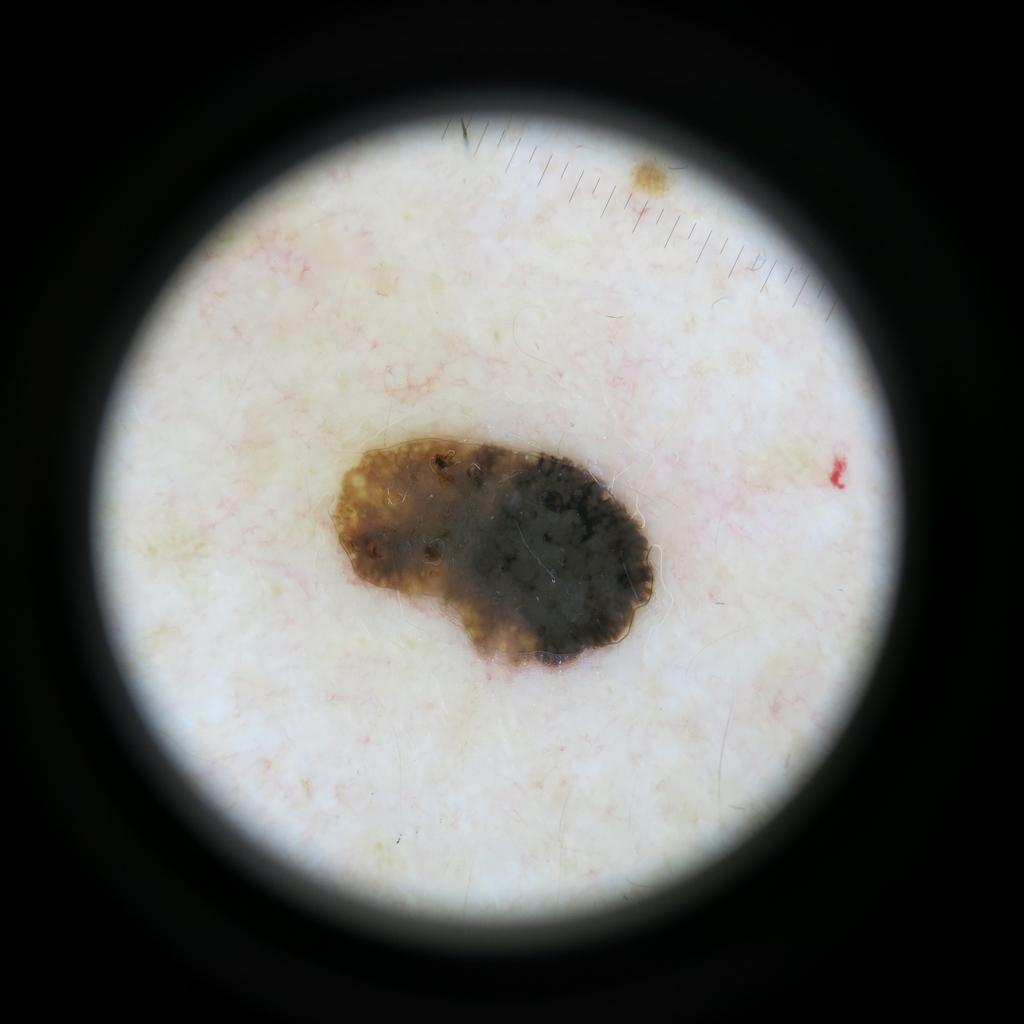

Case: 59

To view the image full-screen and open it in a new tab, please click on the image (thumbnail).